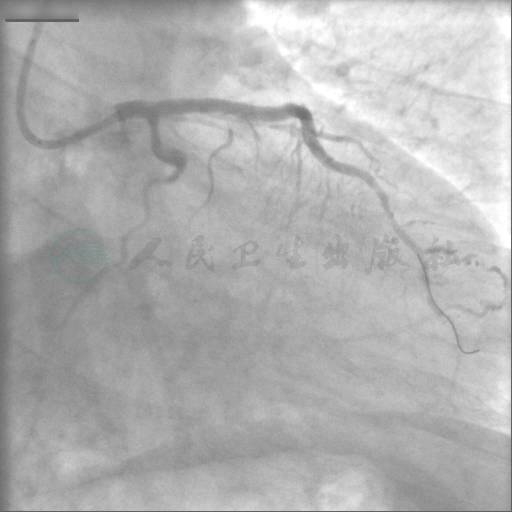

选用右侧桡动脉路径,6F血管鞘。造影发现:前降支近段狭窄90%伴原发撕裂,中段长病变狭窄80%,回旋支大OM开口完全闭塞,前降支经对角支至回旋支大OM2级侧支循环形成,右冠脉至回旋支大OM1~2级侧支循环形成(图1~图6)。

图1 左冠造影1

图2 左冠造影2